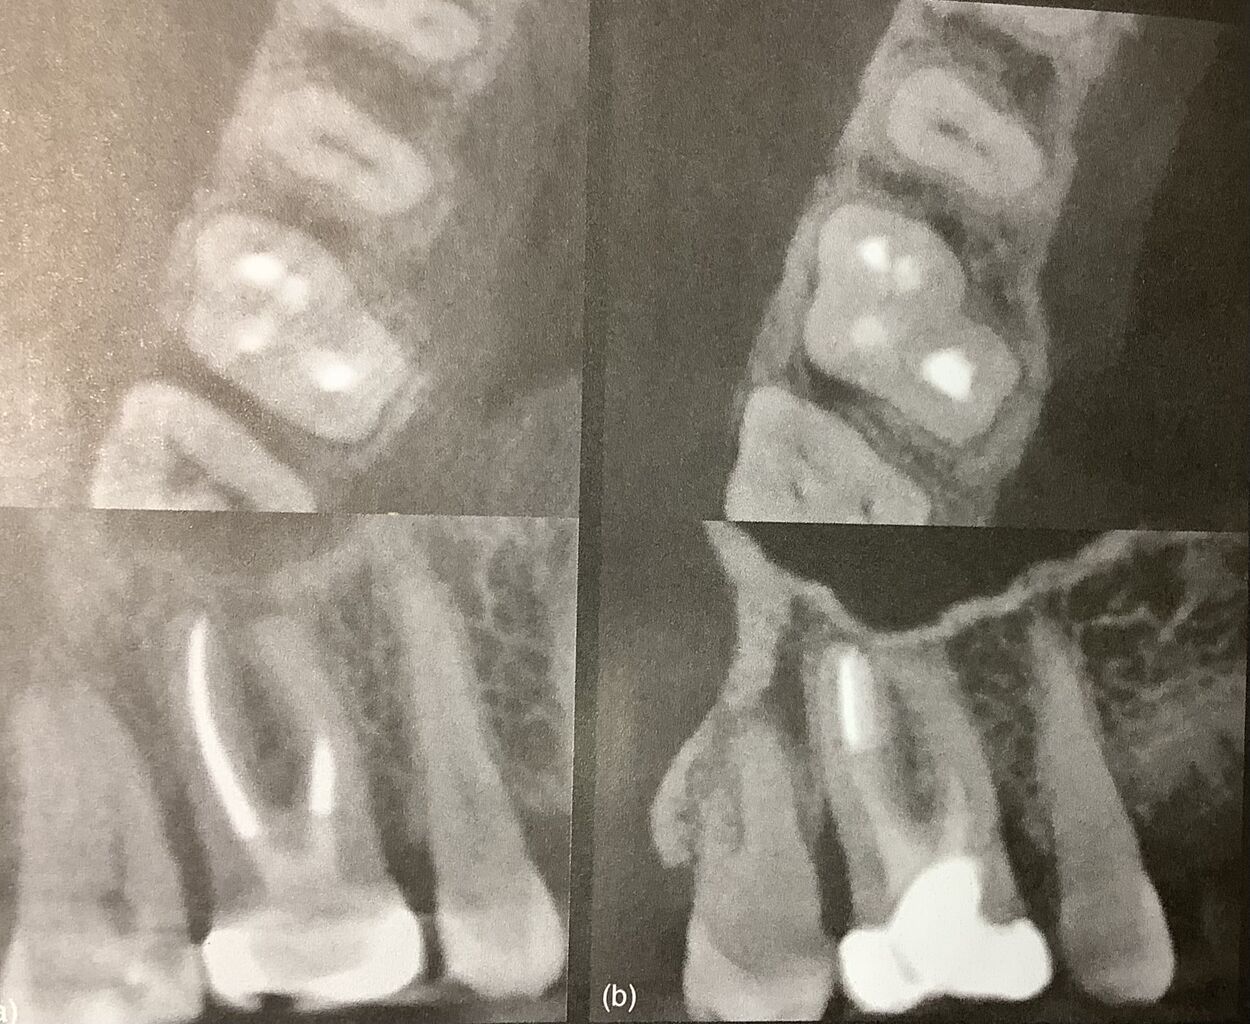

左は治療後3年

右が7年後だそうです。

骨が下がっている所がヒビのあった部分で変化がありませんね。

また根っ子の先まで削れずに短いですが、

でも根っ子の先に影はありませんね。

左は治療後3年右が7年後だそうです。